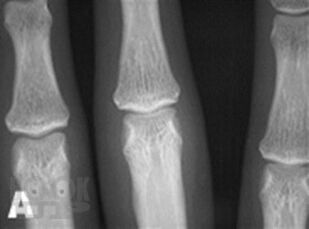

Современные возможности диагностики ревматических заболеваний

В учебном пособии изложены современные представления о методах диагностики ревматических заболеваний. Учебное пособие оснащено тестовыми заданиями и ситуационными задачами различной степени сложности для самоконтроля знаний с эталонами ответов. Учебное пособие предназначено для самостоятельной аудиторной и внеаудиторной работы студентов, обучающихся по специальности «Лечебное дело».